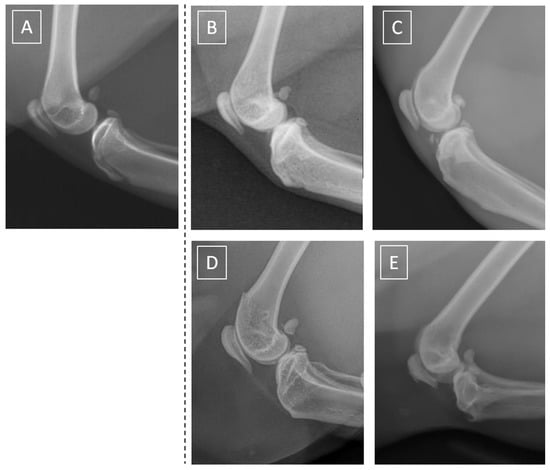

| Score | Severity | Radiographic Signs |

|---|---|---|

| 0 | normal | normal width and shape of the joint space; smooth cortical bone surface; normal subchondral bone pattern; no periosteal proliferation; no intra-articular mineralization |

| 1 | minor | normal width and normal or irregular joint space; normal or irregular cortical bone surface; smooth subchondral bone pattern; flat periosteal proliferation; minor intra-articular mineralization |

| 2 | mild | narrow and irregular joint space with osteophytes; irregular cortical bone surface with well-defined protuberance; smooth subchondral bone pattern; flat periosteal proliferation; mild intra-articular mineralization |

| 3 | moderate | narrow and irregular joint space with multiple osteophytes, enthesiophytes, and marked asymmetry; irregular cortical bone surface with well-defined bone proliferation; subchondral bone cyst; flat periosteal proliferation; moderate intra-articular mineralization |

| 4 | severe | completely narrow joint space with large osteophytes and enthesiophytes; severe deformation of cortical bone surface; subchondral bone sclerosis; flat or intense periosteal proliferation; severe intra-articular mineralization |